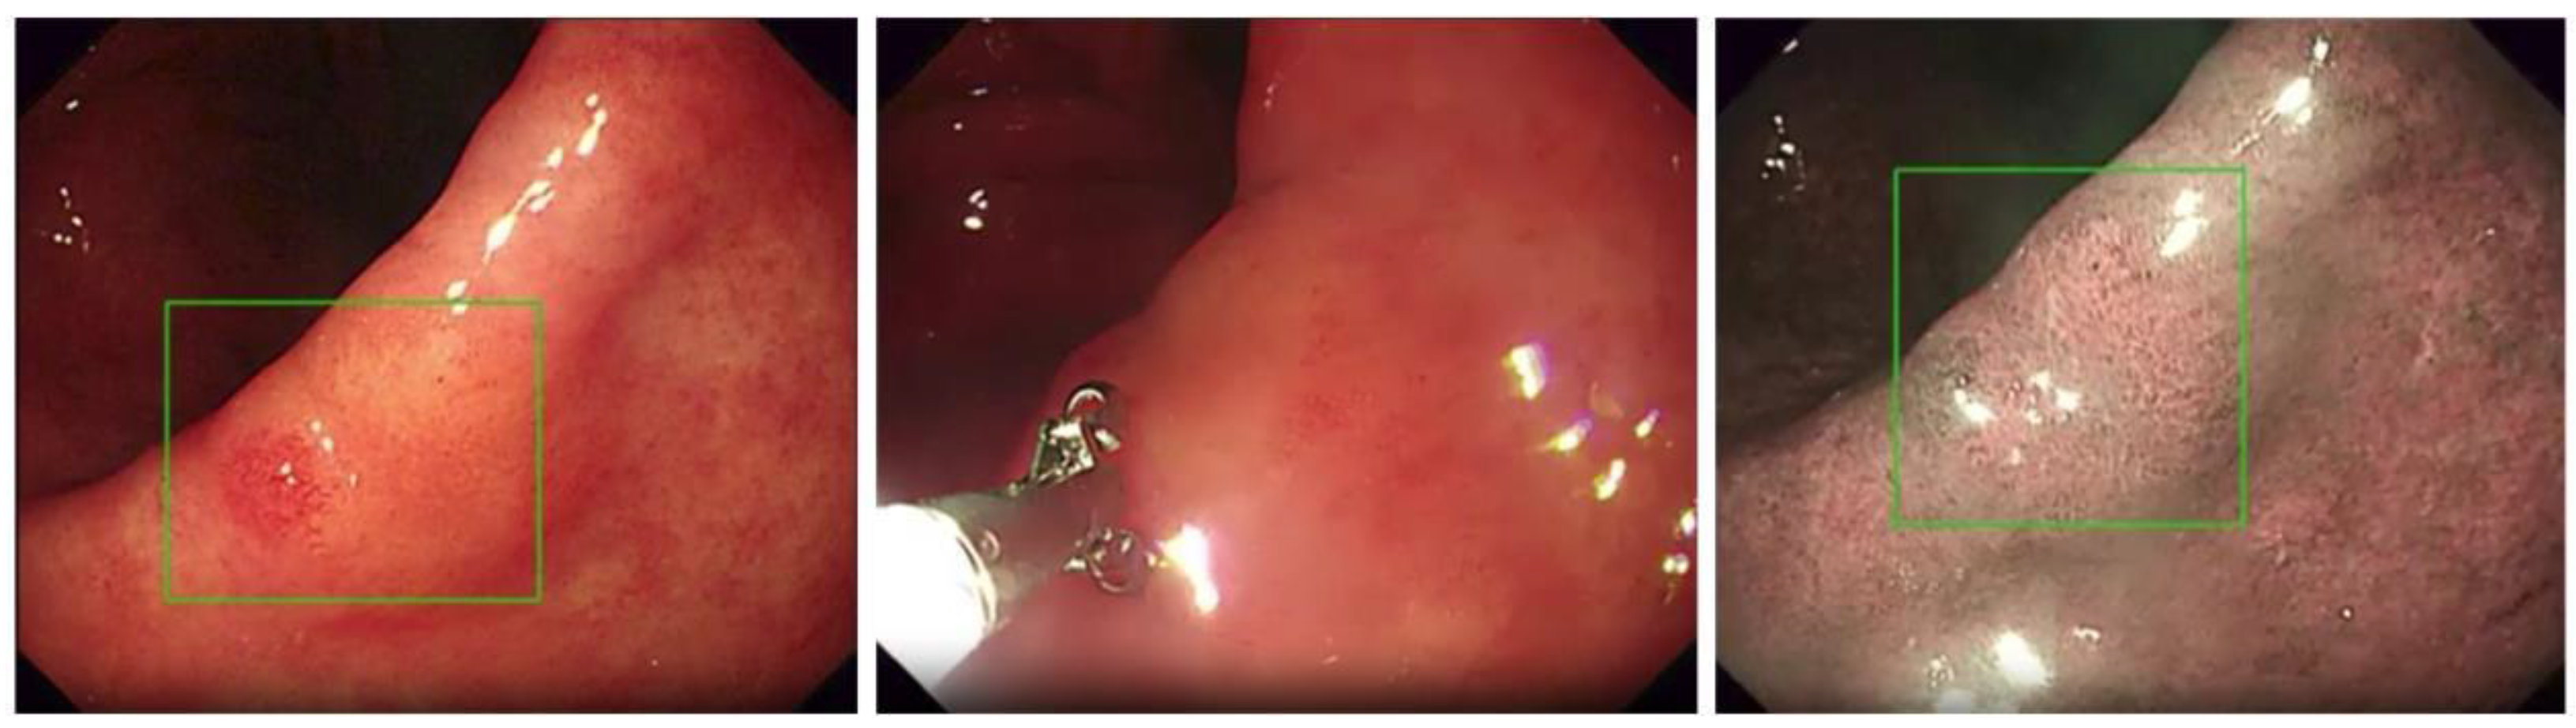

- Gong, E.J.; Bang, C.S.; Lee, J.J.; Baik, G.H.; Lim, H.; Jeong, J.H.; Choi, S.W.; Cho, J.; Kim, D.Y.; Bin Lee, K.; et al. Deep learning-based clinical decision support system for gastric neoplasms in real-time endoscopy: Development and validation study. Endoscopy 2023, 55, 701–708. [Google Scholar] [CrossRef]